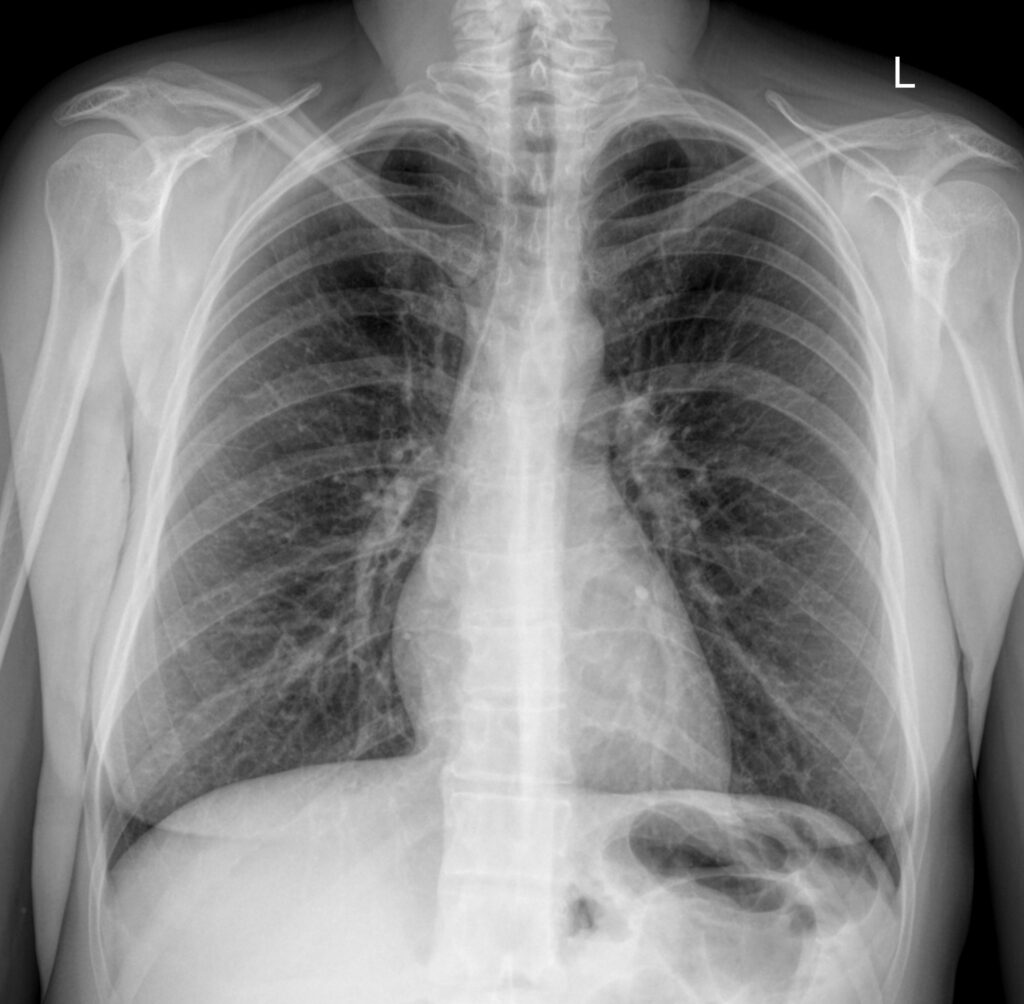

При проведении рентгенографии легких в качестве носителя информации выступает рентгеновская пленка, где изображение крупное и качественное, и цифровой носитель. Разрешающая способность в несколько раз выше, чем у флюорографии, однако, доза облучения немного выше. Поводом для проведения рентгенографии служит госпитализация в лечебное учреждение или жалобы на проблемы, ассоциированные с дыхательной системой.